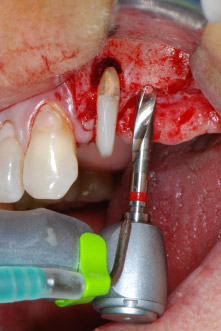

Abb. 8: Der nächste Schritt ist die rotierende Präparation des Implantatbetts bis kurz unterhalb des Sinusbodens an Position 25, die mit einem weiterentwickelten Implantatmotor erfolgte.

Im folgenden Schritt wurde das jeweilige Implantatbett an den Positionen 25 und 26 mit rotierenden Instrumenten in einem Winkelstück mit einem Übersetzungsverhältnis von 20:1 (WS-75 L G, W&H) und einem vor Kurzem aktualisierten leistungsstarken Implantatmotor präpariert (Implantmed, W&H) (Abb. 8 und 19).

Die Abschlusspräparation am Sinus erfolgte wieder mit einem piezochirurgischen Instrument.